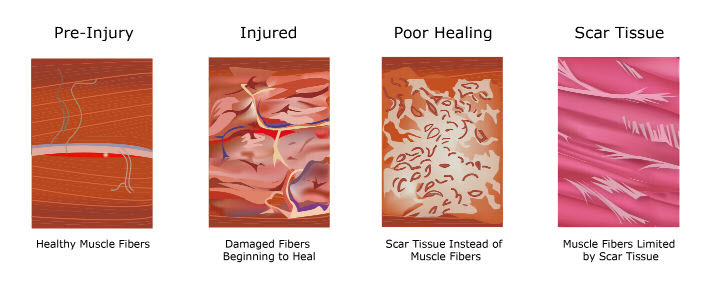

Soft Tissue Therapy In Bristol Takes Sports Massage To A New Level

Ask The Doc What Is Soft Tissue Why Does It Matter

Ask The Doc What Is Soft Tissue Why Does It Matter

Soft Tissue Therapy In Bristol Takes Sports Massage To A New Level